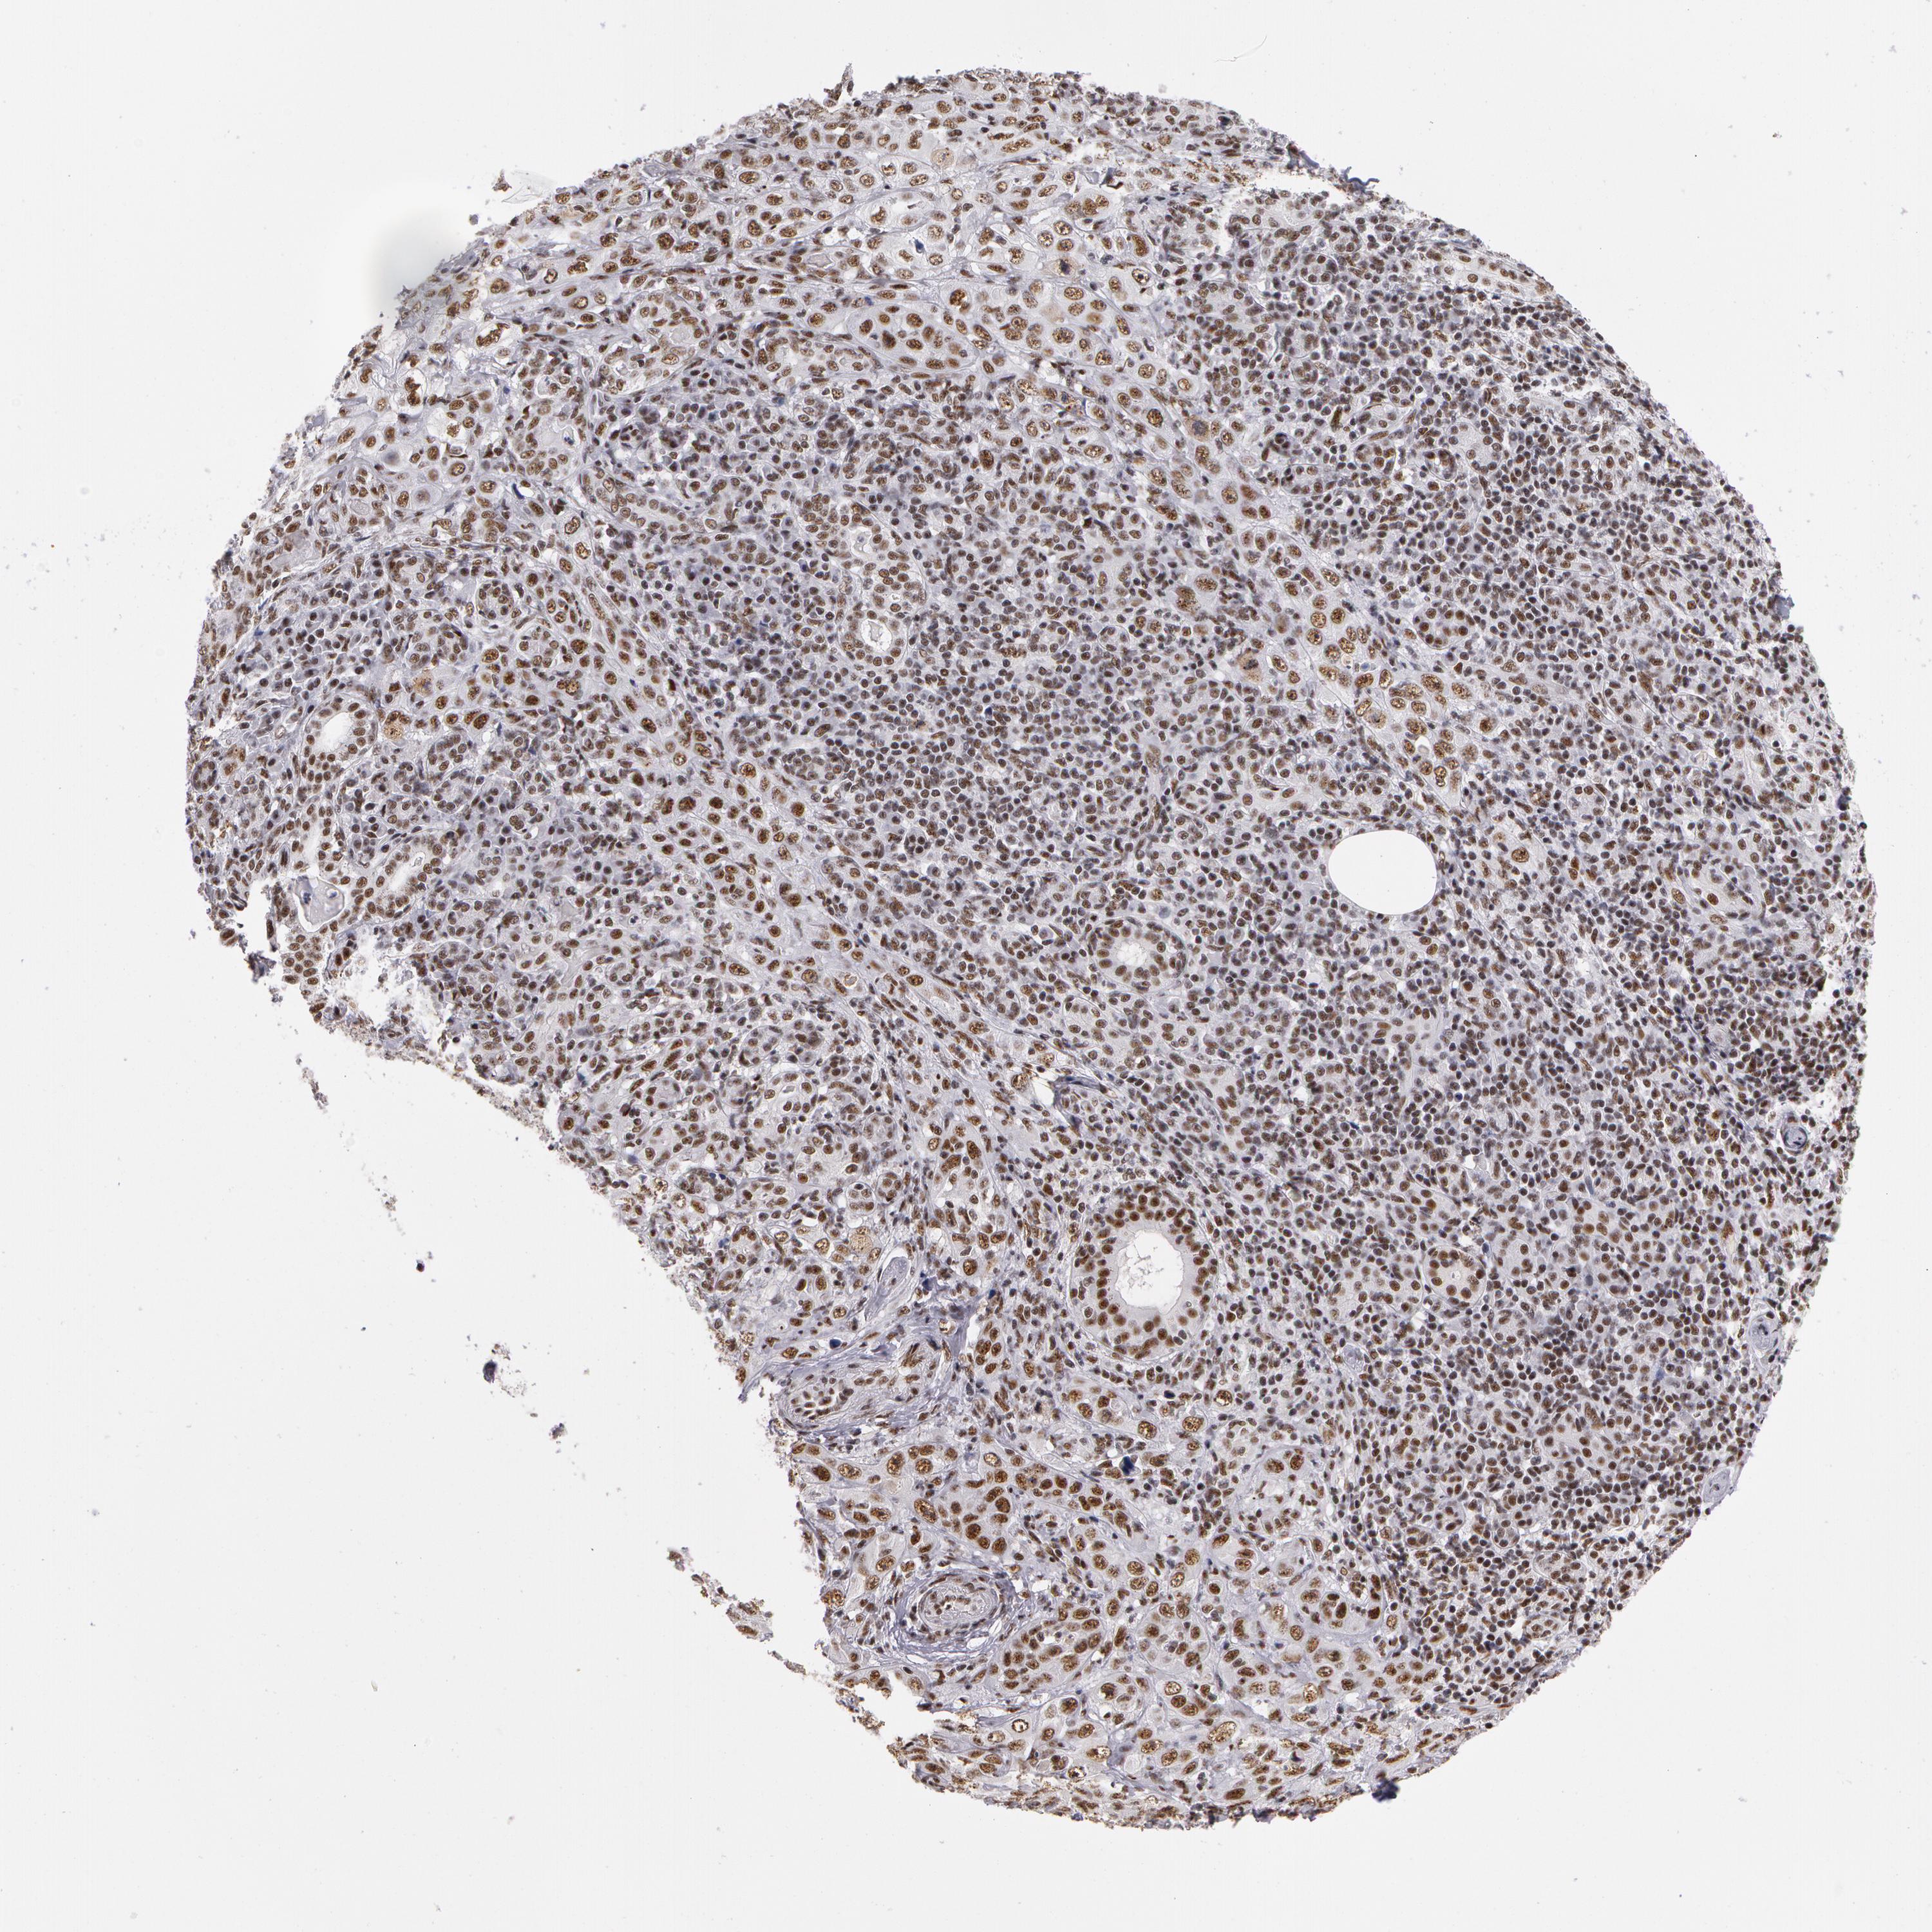

SKIN CANCER - Protein expressioni

A mouse-over function shows sample information and annotation data. Click on an image to view it in a full screen mode. Samples can be filtered based on level of antibody staining by selecting one or several of the following categories: high, medium, low and not detected. The assay and annotation is described here.

Antibody stainingi

Antibody staining in the annotated cell types in the current human tissue is reported as not detected, low, medium, or high, based on conventional immunohistochemistry profiling in selected tissues. This score is based on the combination of the staining intensity and fraction of stained cells.

Each image is clickable and will lead to virtual microscopy that enables deeper exploration of all samples and also displays staining intensity scores, fraction scores and subcellular localization as well as patient and tissue information for each sample.

Antibody HPA001378

Staining

High

Intensity

Strong

Quantity

>75%

Location

Nuclear

Squamous cell carcinoma, NOS